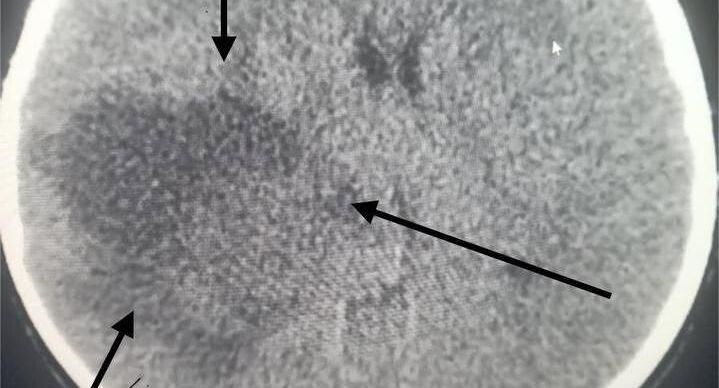

Ребенок поступил в стационар по направлению невролога. В течение суток врачи провели полное обследование, включая мультиспиральную компьютерную томографию головного мозга, которая позволила обнаружить крупное образование в правом полушарии.

Специалисты выяснили, что у ребенка развилась астроцитома — злокачественная опухоль мозга.